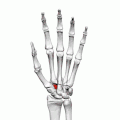

![]() Left hand anterior view (palmar view). Trapezoid bone shown in red. | |

The trapezoid bone (lesser multangular bone) is a carpal bone in tetrapods, including humans. It is the smallest bone in the distal row of carpal bones that give structure to the palm of the hand. It may be known by its wedge-shaped form, the broad end of the wedge constituting the dorsal, the narrow end the palmar surface; and by its having four articular facets touching each other, and separated by sharp edges. It is homologous with the "second distal carpal" of reptiles and amphibians.

The trapezoid is a four-sided carpal bone found within the hand. The trapezoid is found within the distal row of carpal bones.[1] : 708